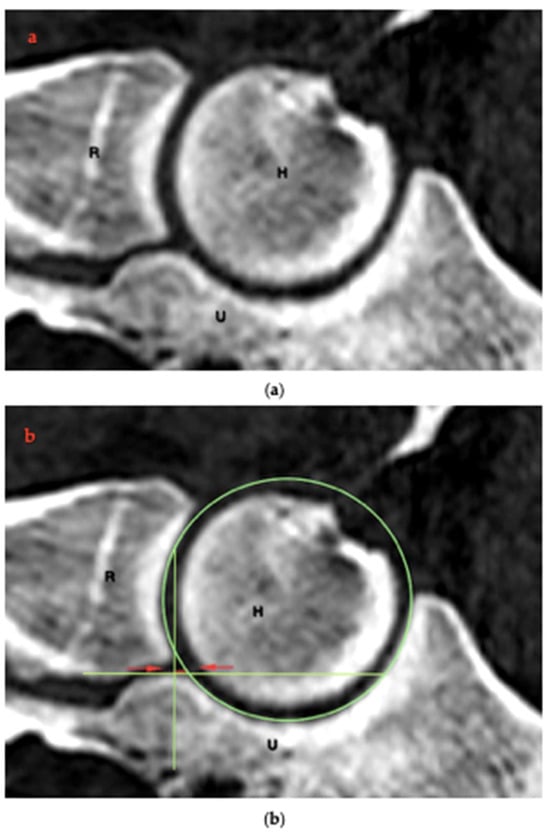

2.4. RUI Measurements